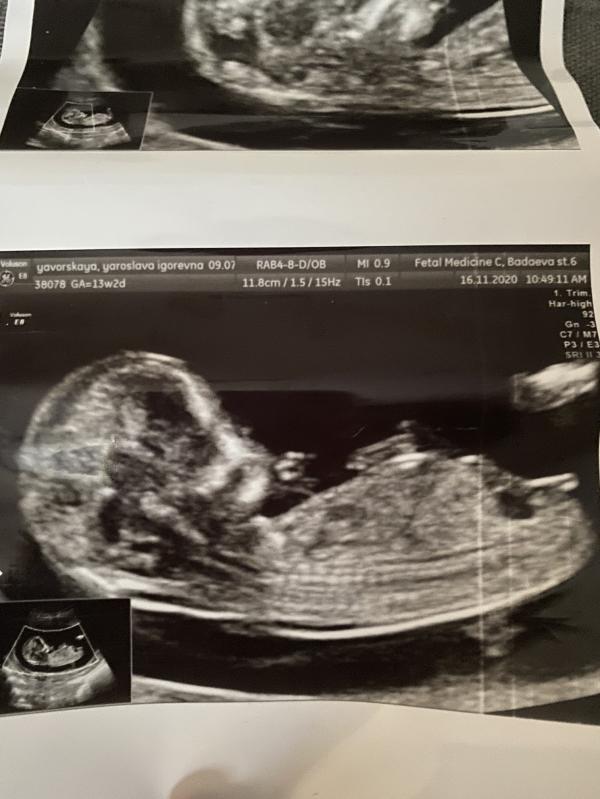

Ну вот,этот день настал!Мы снова ждём ребёнка.Все случилось неожиданно,но ожидаемо😂

Была на первом скрининге и сказали,что скорее всего снова девочка.Муж будет вне себя от восторга,очень хочет ещё дочку.А я вот взгрустнула,так как всегда хотела и сына,и дочь...Уже все прошерстила в интернете и походу да,судя по этому «бугорку половому»-девочка.Эх!а бывают на этом этапе ошибочки?😂

Просто делала у «профи» в этих делах,у Саурского.Говорят,что он очень редко ошибается...а вдруг?😅